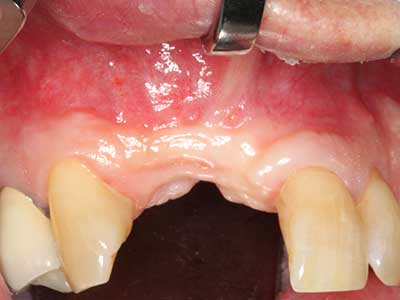

Fig. 12: After six months of healing, the alveolar ridge is vital and sufficiently dimensioned in all planes.

Fig. 13: Adequate irrigation with the 4-mm residual bone width is essential for this 52-year-old patient during the bone splitting.

Fig. 16: The intraoral conditions are also stable with embedding of the implants in keratinized gingiva.